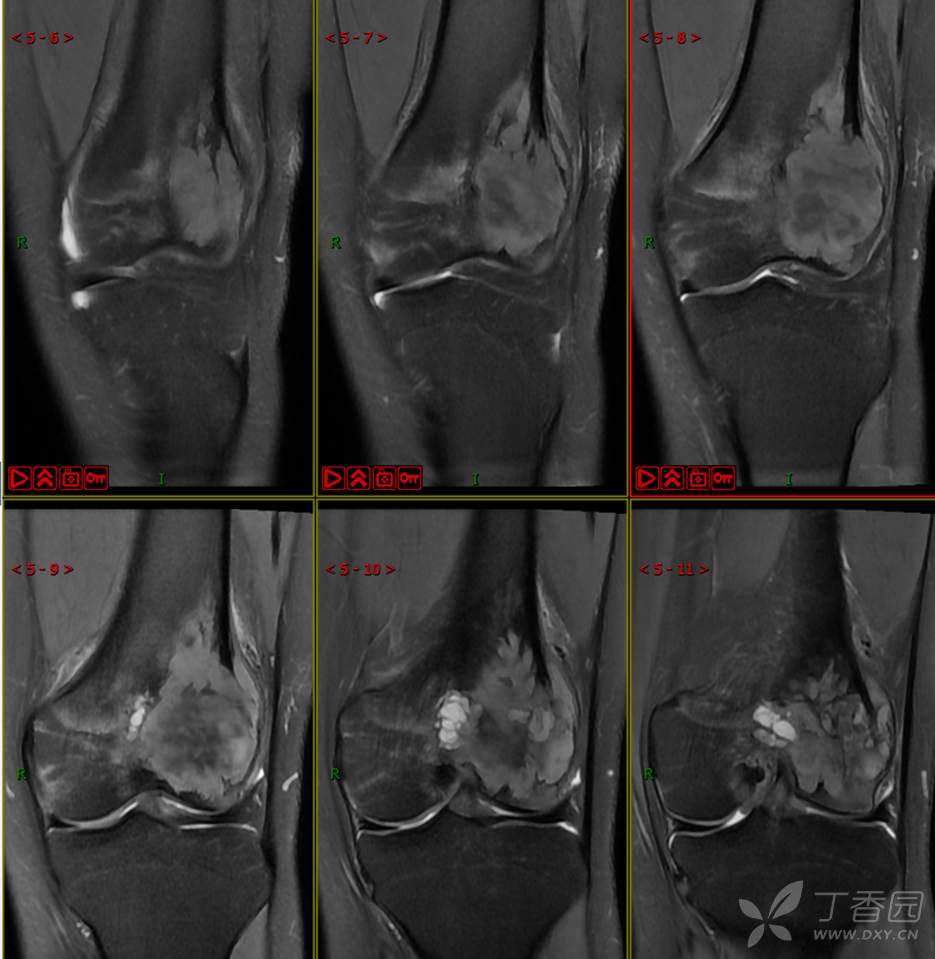

【影诊笔记497】左膝关节疼痛不适1周余就诊,有点难度~『骨巨细胞瘤』

主 诉:左膝关节疼痛不适1周余。

现病史:患者1周余前无明显原因及诱因出现左膝关节疼痛不适,活动时疼痛加重,休息后好转,无明显关节不稳及交锁,无发热、盗汗、乏力,无胸闷、憋气,无头痛、头晕,无四肢小关节晨僵。曾于外院就诊行左膝DR检查示:左股骨远端肿物。现患者为进一步治疗于我院就诊,门诊经检查后以“左股骨远端肿物”收入我科。患者自起病以来,神志清,精神可,饮食睡眠可,大小便正常,体重无明显减轻。